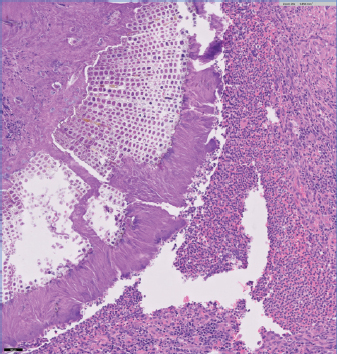

Lesion 2 as seen in Figure 2, there is a segmental area of mucosal thickening with surface ulceration. Coalescing nests of transitional epithelia extend into the underlying superficial submucosa; transitional cells have abundant eosinophilic cytoplasm with distinct cell borders, ovoid-round nuclei with finely stippled chromatin and moderate anisokaryosis and rare mitotic figures. One of the four reviewing pathologists suggested this could be a possible low-grade urothelial carcinoma with a curative clean margin excision.

Fig. 2. Segmental area of mucosal thickening with surface ulceration. Coalescing nests of transitional epithelia extend into the underlying superficial submucosa; transitional cells have abundant eosinophilic cytoplasm with distinct cell border, ovoid-round nuclei with finely stippled chromatin and moderate anisokaryosis and rare mitotic figures. Possible low grade urothelial carcinoma with a curative clean margin excision.